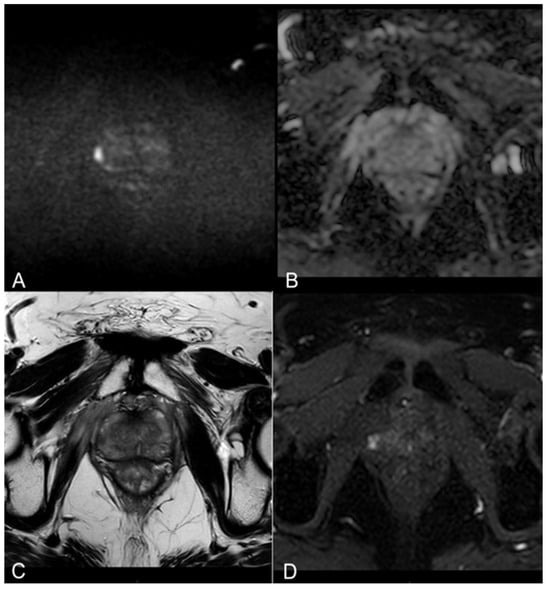

3.2. mpMRI-Derived Results